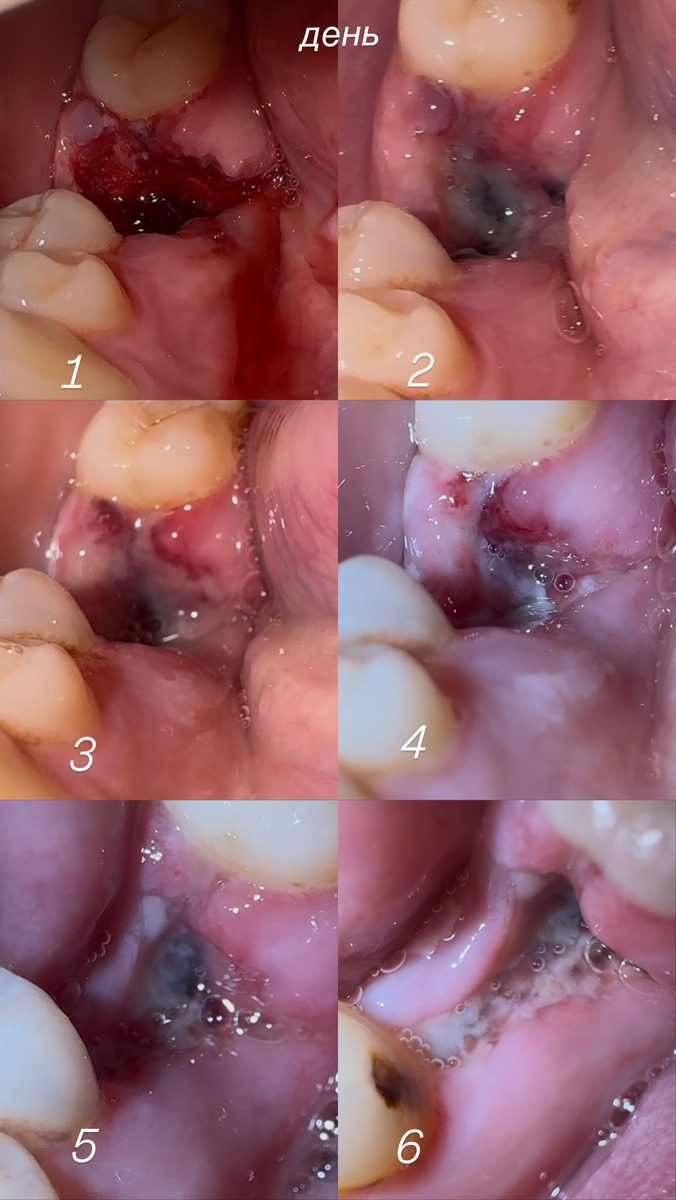

фото , которое я делала каждый день

очень сильно болела лунка , десну он мне всю порезал , ранка просто огромная , 4 дня я кушала через трубочку , чтобы не попала еда в лунку ,сегодня 6 день после удаления зуба , пузырьки пока прошли не все , еще на антибиотиках , ранка иногда поднывает , и щека еще немного опухшая в зоне десны или кости , не знаю

очень переживаю , еще увидела на фото , каждый день фотографировала , что образовался кариес с соседним зубом